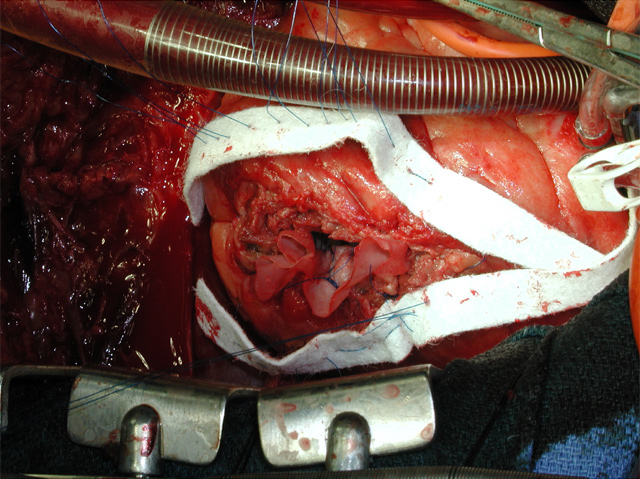

An anterolateral left ventriculotomy is made through the area of infarction parallel to and two centimeters away from the left anterior descending artery. Stay sutures can be placed through the edges of the ventriculotomy to maintain an open visual field. The interventricular septum, area of infarction, and site of rupture are visualized (Figure 3).

The necrotic portion of the septum is inspected but no debridement is necessary. The defect is not closed rather it is excluded from the ventricular cavity (Figure 4).